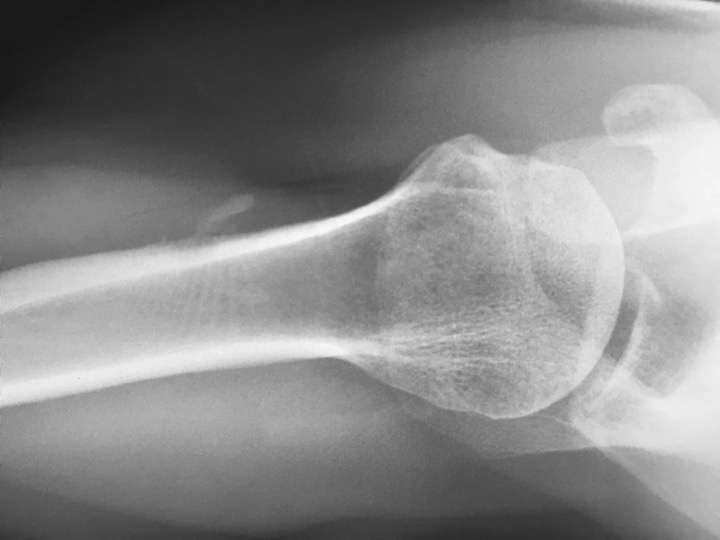

Fell 2 months earlier with minor persistent symptoms, acutely worse x 3 days opening a door. He reported night pain and pain with reaching. 80% improved after 2 days on Medrol dose pak. MRI shows subcortical humeral shaft marrow and parosteal edema with dark signal foci in the region of the pectoralis major insertion. CT shows both peri-tendinous calcifications as well has HADD deposits eroding through the cortex and into bone. Axillary XR clearly shows the peri-tendinous deposit; the cortical erosion is faintly visible....and I expect you can all see the intra-osseous calcific deposit.

tendon of pectoralis major ( RID2007 )